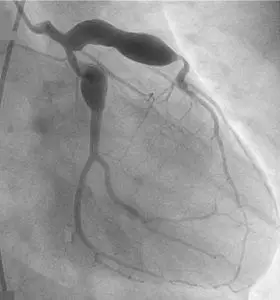

Hastalığın son aşamasında ise belirtiler ortadan kalkabilmektedir. Bununla birlikte tedavi uygulanmadığı takdirde çocuklarda kalp komplikasyonları görülebilmektedir. Bu komplikasyonlar hastalığın en önemli ve ciddi semptomlarıdır. Kalpte aritmiler ve çeşitli katmanlarda iltihaplanmalar görülebilse de hastalığın yarattığı en büyük hasar kalp damarlarında genişlemedir (anevrizma).

Yeni Coronavirüs vakalarının en çok görüldüğü ülkeler arasında İtalya, İngiltere ve Amerika bulunmaktadır. Özellikle Kuzey İtalya ve İngiltere’nin bazı bölgelerinde, bu dönemde Kawasaki hastalığının bazı bulguları ile gelen çocuk hasta sayısında artış olduğu bildirilmiştir. Çocuklarda görülen bulgular arasında yüksek ateş ve koroner arter anevrizması bulunmaktadır. Özellikle 9 yaşından küçük çocuklarda bu semptomların artış göstermesi Yeni Coronavirüs ve Kawasaki hastalığı arasında bir ilişkinin olduğundan şüphelenilmesine neden olmuştur.

Hastalığın tedavisinde öncelikle aspirin ve yüksek dozda intravenöz immünoglobülin uygulanmaktadır. Antikor olarak da bilinen intravenöz immünoglobülin, insan kanının sıvı bölgesinden elde edilen saf plazma anlamına gelmektedir. Aspirin ve özellikle enfeksiyon tedavilerinde sıklıkla kullanılan intravenöz immünoglobülin birlikte uygulanarak iltihapların ve hastalığın hızlı ilerleme gösteren belirtilerinin azaltılması amaçlanmaktadır. Aynı zamanda, hastalığın son evresinde görülen koroner damar genişlemesinin ortaya çıkma olasılığını en aza düşürmek amacıyla da bu tedavi yöntemi uygulanmaktadır.

Çoğu hasta için bu tedavinin uygulanması yeterli olmaktadır. Bununla birlikte, bazı çocukların intravenöz immünoglobülin tedavisine yanıt vermemesi nedeniyle alternatif tedavi yöntemlerine geçilmektedir. Damar içi kortikosteroid verilmesi bu yöntemlerden biridir. Özellikle koroner arter anevrizmalarında kortikosteroid sıklıkla uygulanmaktadır. Halk arasında kortizon olarak da bilinen bu tedavi yöntemi iltihapların azaltılmasına yardımcı olmaktadır.

Tedavi başladıktan 24 ila 48 saat sonrasında çoğu hastada yüksek ateş gerilemektedir. Bu noktada hastalara uygulanan aspirinin dozu azaltılmaktadır. Tedavi sırasında düşük dozda da olsa aspirin verilmeye devam edilmesinin en önemli nedenlerinden biri iltihap görülen koroner arterde kan pıhtısı oluşumunun önüne geçmektir. Kalp damarlarındaki genişlemenin gerilemesi sonrası ilaç tedavisine son verilmektedir.